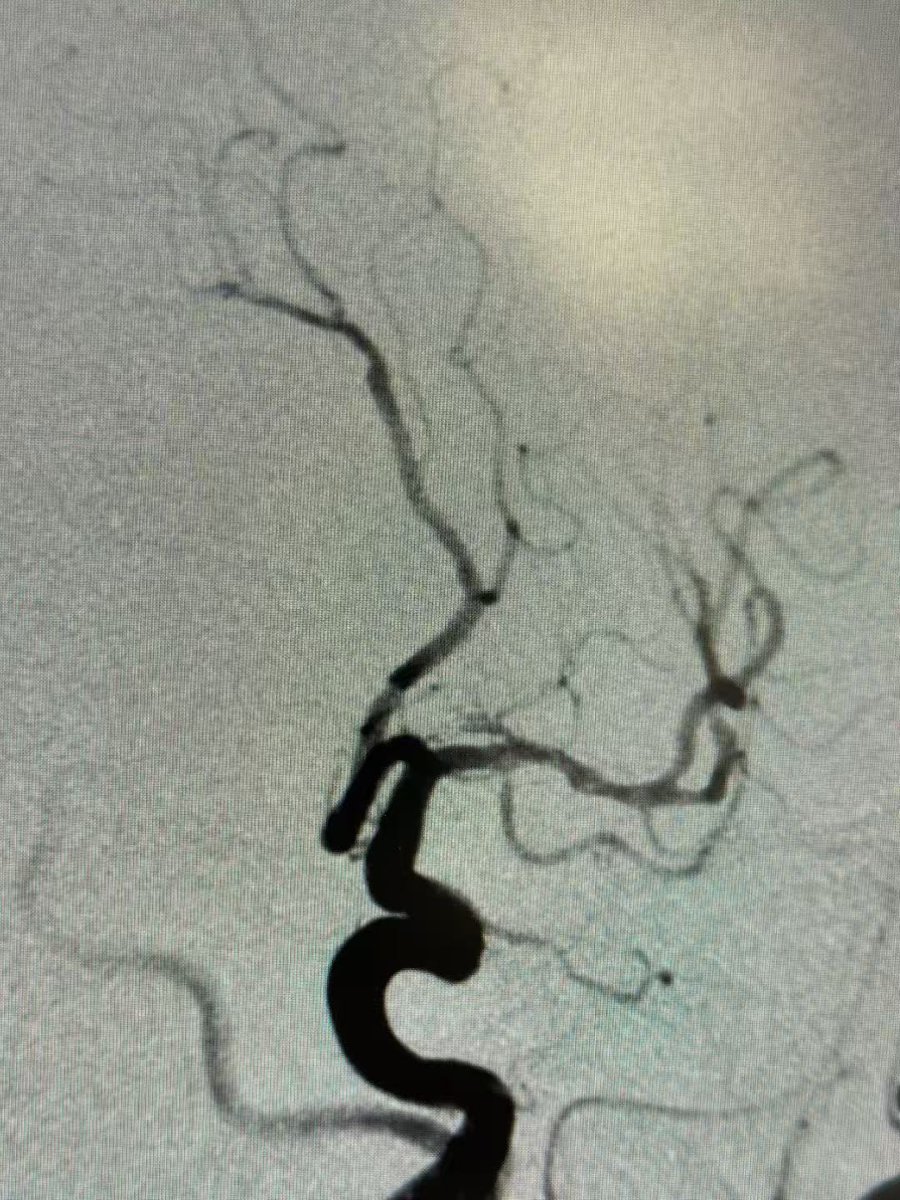

This 🧔♂️ presents with a subarachnoid haemorrhage in the left suprasellar cistern

DSA shows an infundibulum/ aneurysm of the left PCom. To coil or not was a conundrum. Every expert has a different take

The size is 3.4 mm x 2.6 and it is located in the region of the bleed.

What would you do?